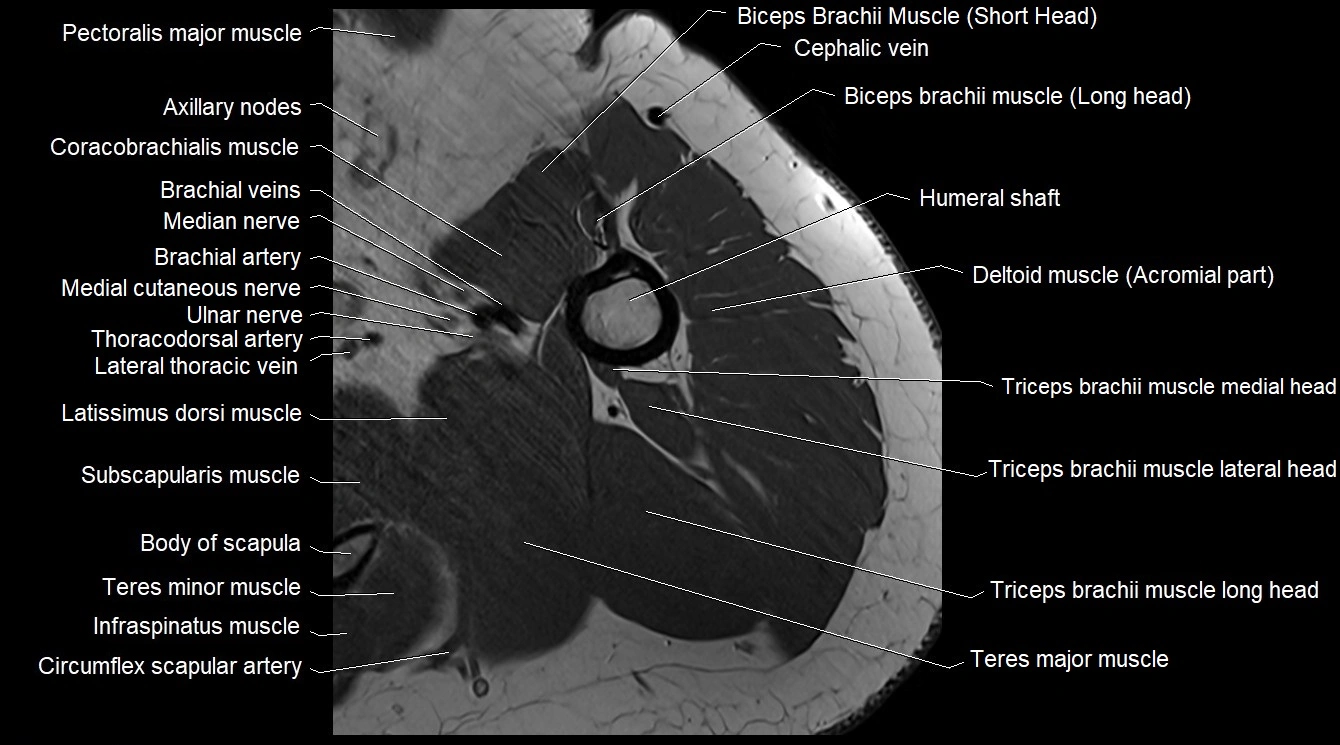

MRI image